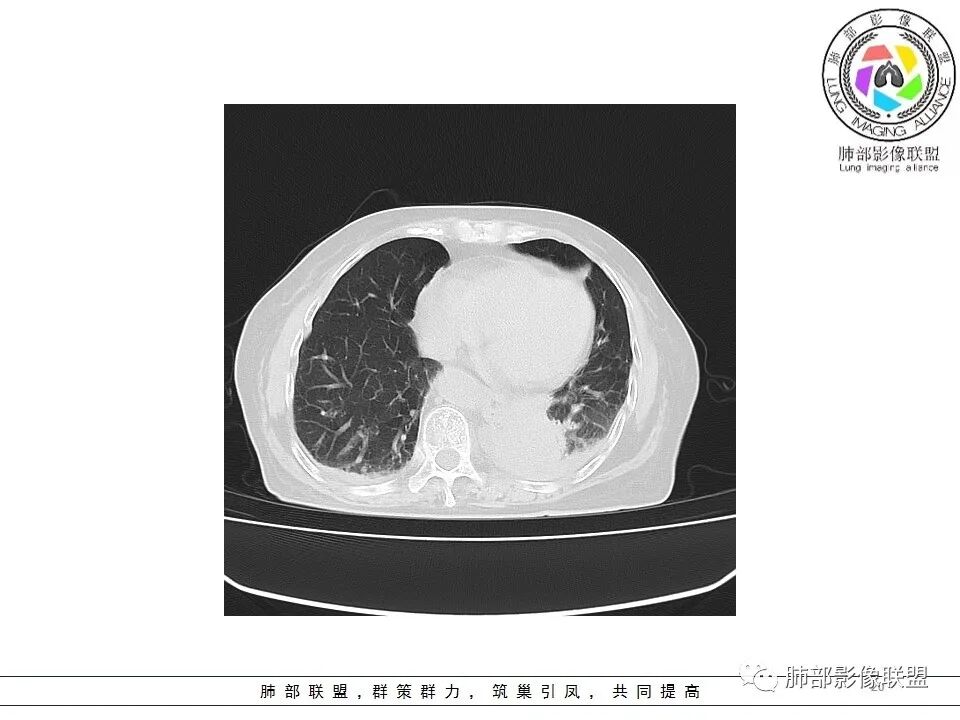

一切∮随缘: 左肺下叶脊柱旁可见大片状实变,跨多个叶段,宽基底与胸膜相贴,胸膜下可见积液,周围伴有空洞,平扫密实欠均匀,增强扫描可见低密度坏死,及血管束穿行,临床:女性,反复咳嗽咳痰7天,余未提示异常,无实验室指标,考虑:慢性脓肿(OP),放线菌?奴卡?腺癌?完善支气管镜,穿刺送培养,病理学检查。

?? 玫: 女,78岁,反复咳嗽,咳痰一周,左侧胸腔积液,贫血,左肺下叶片状实变影,边界清晰,病灶呈宽基底与胸膜相连,病灶内密度不均,增强扫描呈不均匀性强化,病灶内坏死,考虑肺脓肿可能,鉴别鳞癌,腺癌。

不吝慷慨: 左下肺肿块样病变,好像有体循环供血,肿块内血管漂浮,基本走行自然,所以综合考虑肺段隔离症,有低密度坏死区及胸腔积液,考虑合并感染。鉴别一下淋巴瘤

宇宙: 左肺下叶后基底段肿块,边缘毛糙,后基底段支气管阻塞,明显不均匀渐进强化,其内血管清晰自然,可见坏死灶,部分边界清,左侧胸水,考虑炎性病变,鉴别腺癌

飞鹰行动: 女,78岁,反复咳嗽,咳痰七天,左肺下叶纵膈旁团片状实变影,边界清晰,局部膨胀性生长,病灶内密度不均,增强扫描病灶内呈不均匀性强化,部分坏死区边界不清晰,内可见血管造影征,部分坏死区边界清晰,可见环形强化,感染性病变是有的,需要警惕合并占位,腺癌伴感染?

小兜: 女,78岁 反复咳嗽咳痰7天,左肺下叶脊柱旁实变影,平扫密度不均,内部可见低密度灶,增强扫描明显不均匀强化,内部血管走行自然,可见多发低密度坏死区,坏死区边界清晰,少量胸水,考虑脓肿

风儿: 老年女性,咳嗽咳痰7。左肺下叶后基底段肿块,边缘毛糙,外缘轻度膨隆,支气管有阻塞,强化不均匀,其内血管清晰自然,可见边缘清晰坏死灶,少量胸水,考虑:炎性-炎症机化伴慢性脓肿、放线菌;肿瘤:腺癌

老年女性,急性发病,短病程病史。左肺下叶实变影,肺叶体积缩小,周围有带状不一致密度影。单独发生于左侧的胸腔积液渗出液多见。   影像上病灶重建后长轴呈楔形,而非类圆形,边缘平直,符合肺叶形态(与横断位膨隆并不一致),从整体形态上支持炎性病变;   病灶内血管走形自然,无受侵犯、受推移迹象,不大符合鳞癌等破坏性较强的肿瘤性病变。女性患者鳞癌也少见。   病灶内坏死腔内壁清楚光滑,薄环状强化带,支持炎性、尤其是化脓性病变。肺腺癌这样的坏死少见。   病灶近端支气管虽然堵塞,但是支气管走形自然,壁无明显破坏,腔内粘液栓堵塞为主,病灶外周大,内带小,局部无膨隆迹象,不符合近端支气管肺癌堵塞所致表现;也不符合外周肿块朝内带推进表现。   综合分析:符合炎性病变,不支持恶性肿瘤性改变